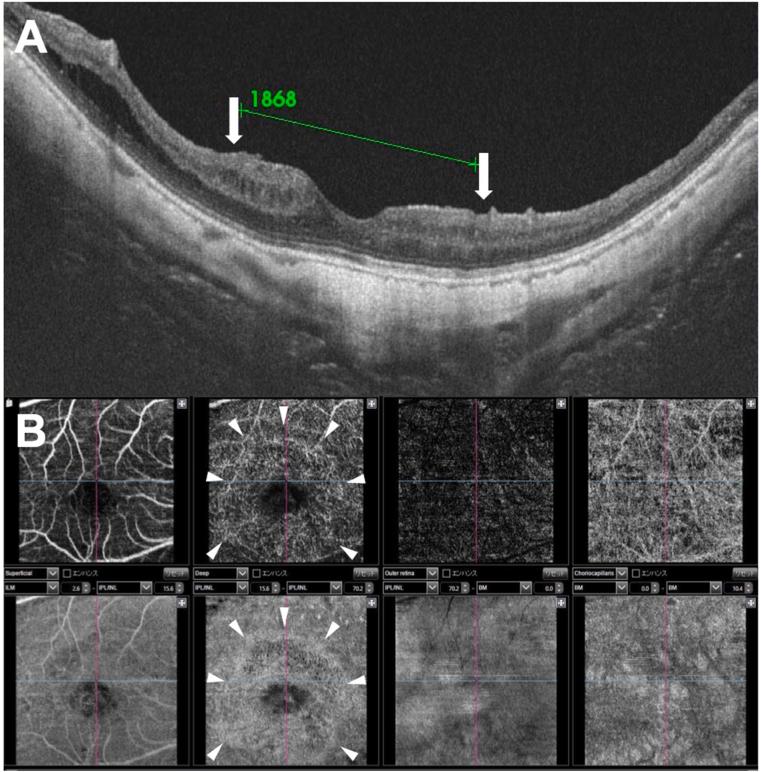

A 63-year-old man diagnosed with foveoschisis and a small outer lamellar macular hole underwent 25-gauge, 3-port pars plana vitrectomy and fovea-sparing ILM peeling using indocyanine green (ICG) staining. One year after the vitrectomy, optical coherence tomography (OCT) revealed a resolution of the macular retinoschisis and an intact ellipsoid zone at the fovea. However, macular edema was present over the area of the residual ILM, and the visual acuity had worsened to 20/200. Goldmann perimetry showed a central scotoma and a constriction of the nasal visual field. OCT angiography detected abnormal blood flow in the inner retina corresponding to the area of the residual foveal ILM. The multifocal electroretinograms were reduced in the central area.